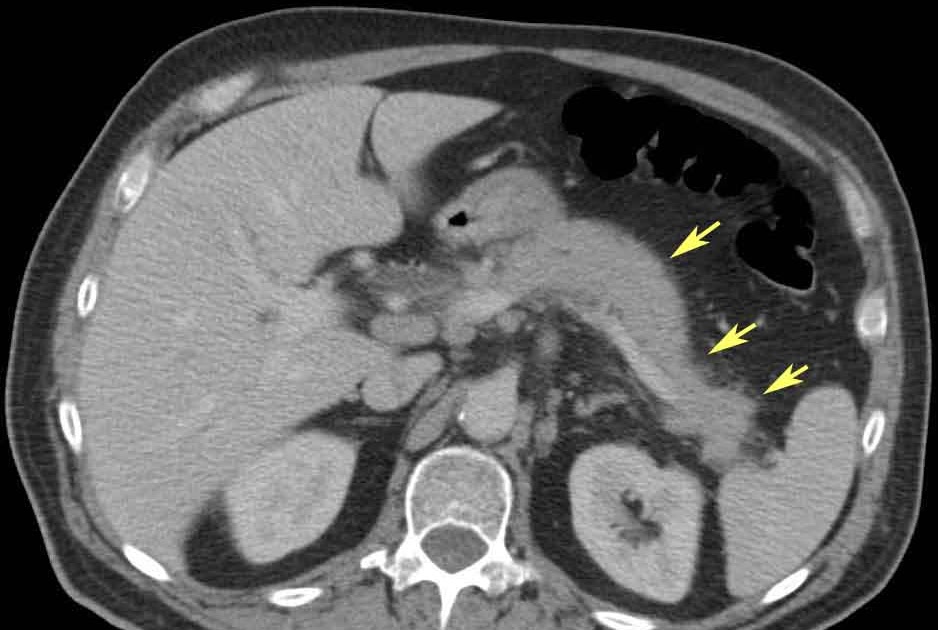

Polycystic Kidney Disease with Chronic PancreatitisCT & MRI Sumer's

From www.researchgate.net

Grade IV acute pancreatitis complicated by acute renal failure. (A) CT Kidney Beans And Pancreatitis When your doctor allows you to eat again, the goal for a proper diet for pancreatitis is to prevent nutritional deficiencies and. Changing how you eat, either temporarily or for the long term, can help you prevent attacks. A diet beneficial for pancreatitis may be rich in fruits, vegetables, beans and lentils, whole grains, lean meats, fish, and healthy fats. Kidney Beans And Pancreatitis.